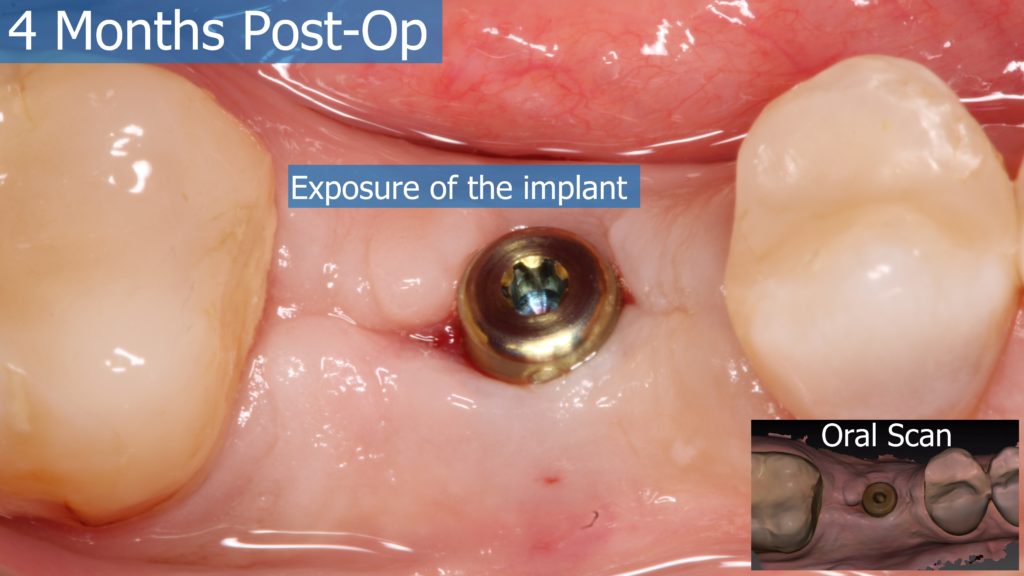

A healthy 36 year old woman comes to the clinic with pain and swelling in the area of the inferior left molars. In the intraoral observation, a vestibular fistula was identified, and the complementary exams confirmed a bone lesion caused by a root perforation (poorly executed false post) on the first lower left molar #36 (19). It was decided to do antibiotic therapy for a week and then the tooth extraction with immediate implant placement and bone graft. 4 months post-op the definitive zirconia/ceramic crown would be was made.